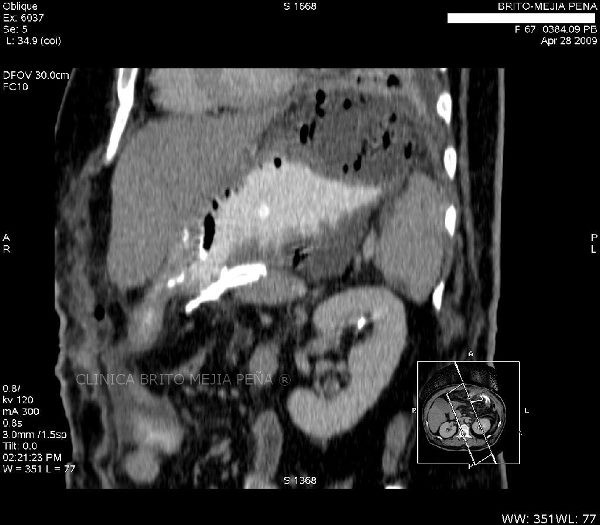

Colangiocarcinoma oblicua